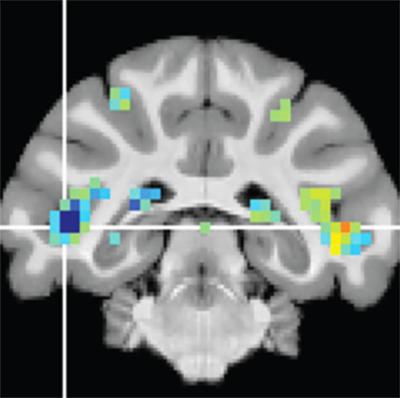

Krauzlis and his colleagues described the discovery of the fSTS in a study published last year with David Leopold, Ph.D., chief of the Section on Cognitive Neurophysiology and Imaging at the National Institute of Mental Health. Together they had the monkeys complete the visual attention tasks inside a functional magnetic resonance imaging (fMRI) machine. fMRI imaging revealed that a specific region in the temporal cortex—later named fSTS—was, like the superior colliculus, strongly activated during these attention tasks. This was surprising because this cortical region was not yet known to be important for visual attention.

The researchers directly measured fSTS neurons’ firing in the areas previously revealed by fMRI. These direct measurements revealed that not only is a large proportion of fSTS neuronal activity dependent on the superior colliculus, these neurons use information from the superior colliculus to represent complex visual information.

The fSTS neurons activated in response to “attended” events and changes in stimulus, and their activity strongly correlated with the likelihood that the monkey would report seeing an event. For “ignored” events, the fSTS neurons were much quieter. When the researchers dampened the superior colliculus, the fSTS neurons showed less distinction between attended and ignored events, with lowered activity to attended events and higher activity for ignored events. In other words, the fSTS depends on the superior colliculus to mark which events are important and which are not.